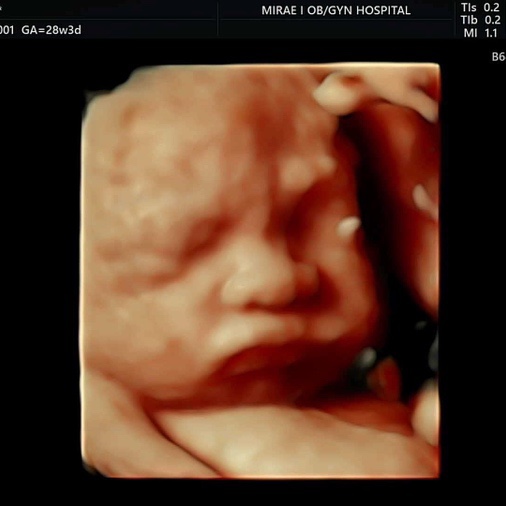

?임신 28주차 | 입체초음파 대성공?? 심바 얼굴 보여주다!

임신 28주차 진료? 병원마다 다르겠지만 미래아이 산부인과는 28주차에 처음 입체초음파를 본다. 얼마나...